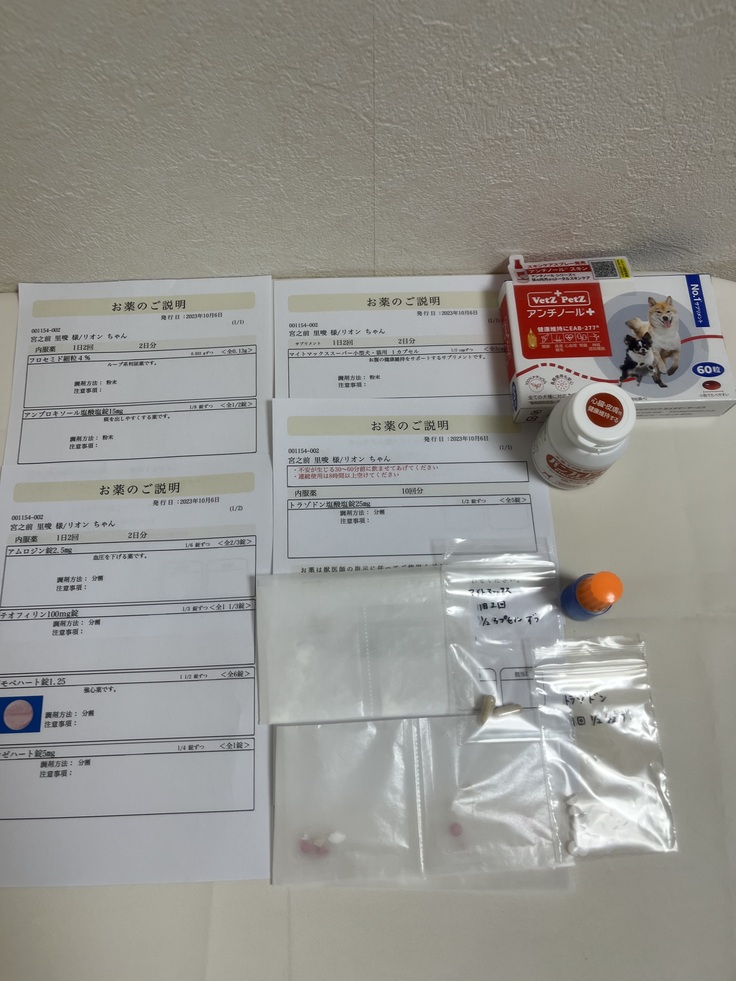

今回出たお薬といつものサプリ💊